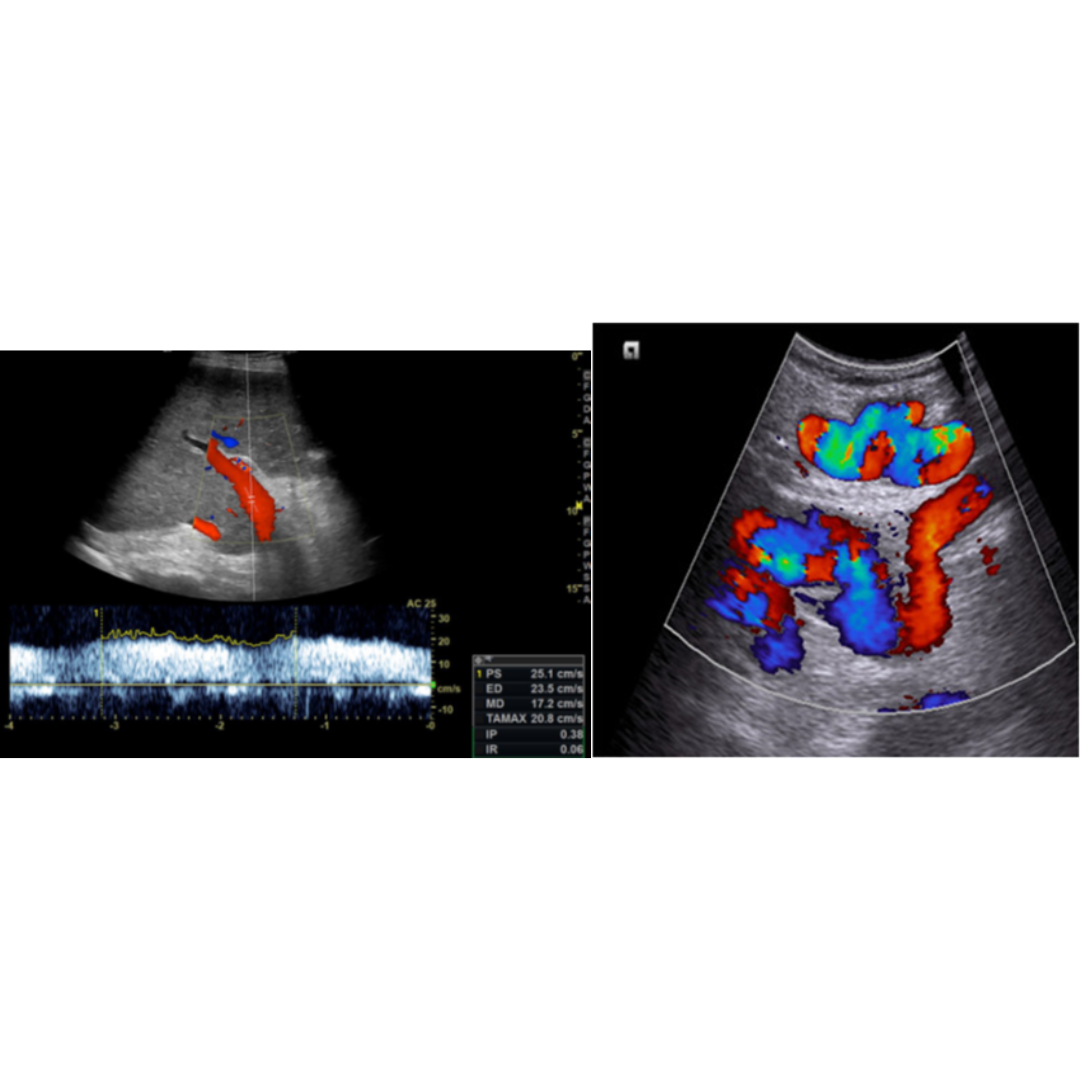

La velocidad portal normal es 15 a 18 cm/s, con el desarrollo de la HP la velocidad disminuye bajo 15 cm/s (figura 7). Las velocidades se verán alteradas por el tipo de colaterales que tenga el paciente. La velocidad media se puede ver aumentada solo en pacientes que presentan recanalización de la vena para umbilical (figura 5-6) y disminuida en pacientes con colaterales espleno-renales (2).

Figura 5-6: Vena porta con flujo hepatopeto, con un estudio espectral con velocidad encima de 25 cm/s, figura 5 paciente con recanalización de vena paraumbilical en paciente con HP severa.